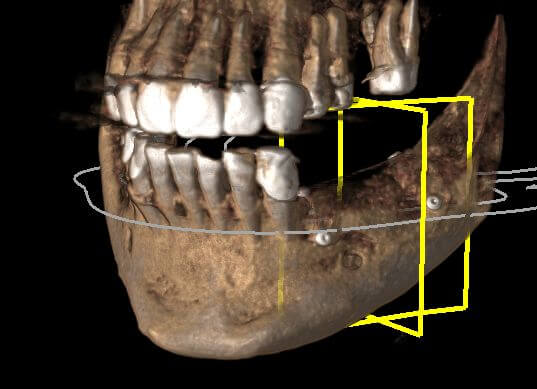

Пациентку не устраивал съемный протез нижней челюсти, который она носила на протяжении нескольких лет. У пациентки на нижней челюсти отмечался выраженный дефицит костной ткани как по высоте, так и по ширине. Без предварительной костной пластики установка имплантатов для несъемной конструкции невозможна. Выполнена костная пластика титановой сеткой.

По контрольной рентгенограмме прирост кости по ширине и высоте. Планируется вторым этапом имплантация на нижней челюсти.